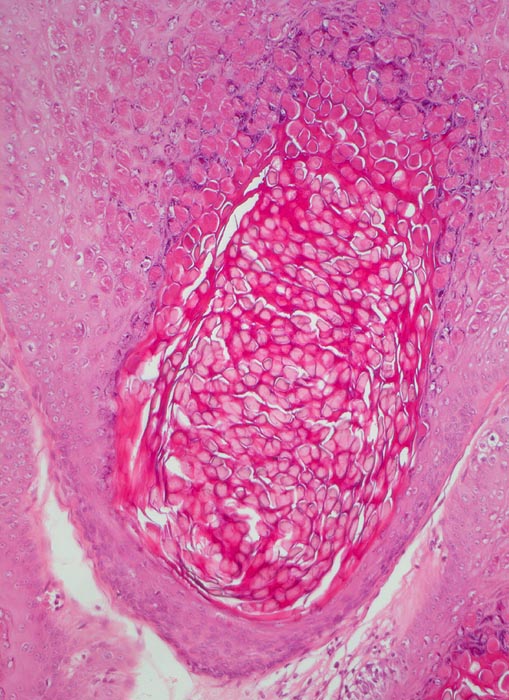

PathoPic ID 5107 - Molluscum contagiosum

Molluscum contagiosum

Haut, Anus

Haut

Kugelige eosinophile intrazytoplasmatische Einschlüsse sind vor allem in Zellen des $o{qy8042178Stratum granulosum} Stratum granulosum und des

Stratum corneum erkennbar.

Perianal kleine linear angeordnete Hautpapeln.

Histologie

100

5

männlich